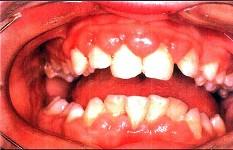

患者,男性,19岁,主诉:前牙牙龈红肿肥大1年余。临床检查:上唇短,上前牙唇侧牙龈边缘及龈乳头增生肥大,覆盖牙冠的1/3,质地较韧。最可能的诊断是 ( )

A.增生性龈炎B.牙龈纤维瘤病C.青春期龈炎D.慢性龈缘炎E.急性坏死性溃疡性龈炎

A

解析